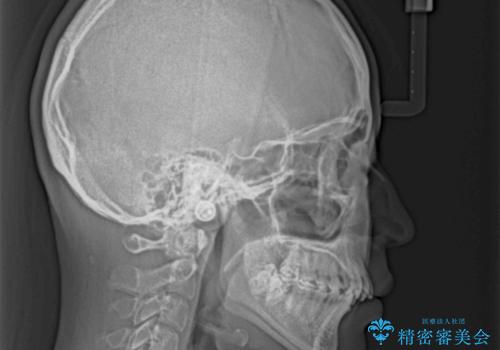

- デコボコになっている前歯を気にして来院された患者様です。

口元の突出感は気になっていないものの、デコボコを解消すると口元が前方に突出する可能性があるため、上下左右の第一小臼歯4本を抜歯して、ワイヤー装置にて矯正治療を行うこととしました。

下の前歯が隠れてしまうほど深く咬みこんでいたため、上顎前歯が前方に突出しているような印象がありましたが、咬み合わせが改善され、整った口元に仕上げることができました。